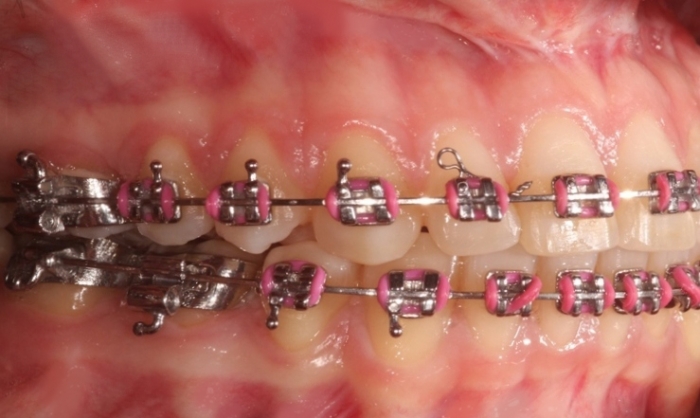

Mordida inicial